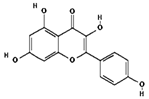

| Quercetin | 5280343 | C15H10O7 | 302.23 | 0.52 | 0.55 | No |  |

| Kaempferol | 5280863 | C15H10O6 | 286.24 | 0.50 | 0.55 | No |  |